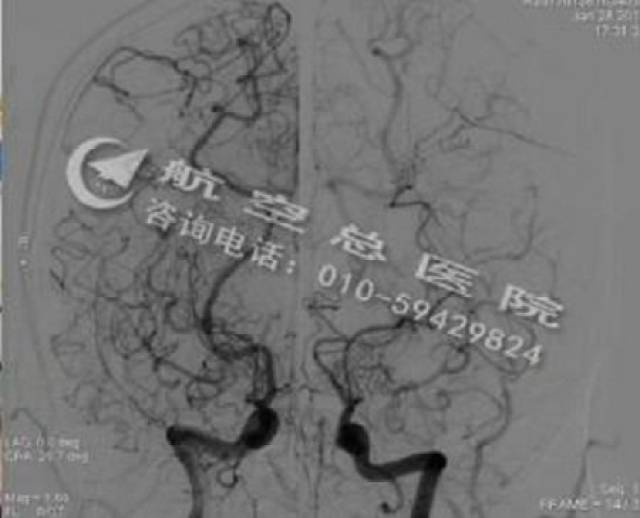

烟雾病引起脑梗怎么治?如何治疗烟雾病

450x364 - 16KB - JPEG